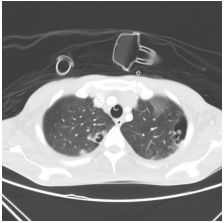

5. 57 y female, breast ca for survey